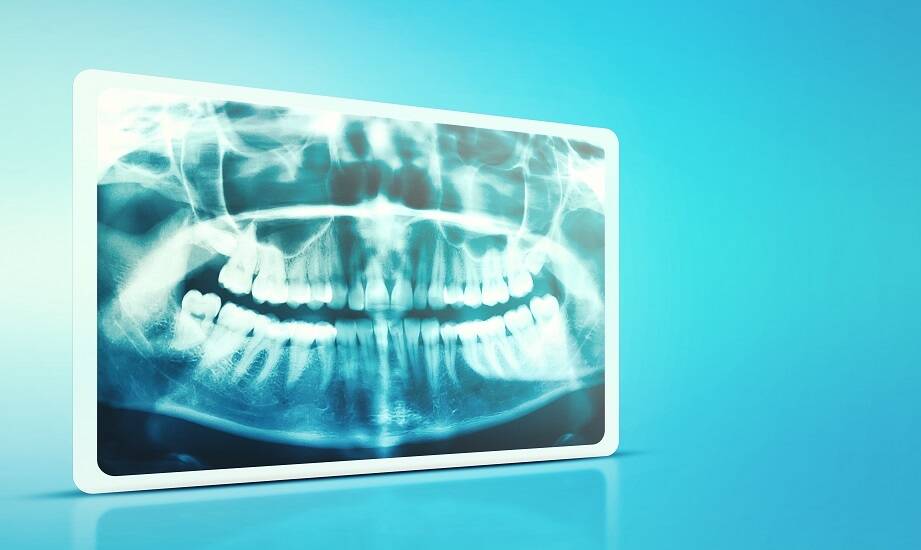

Diagnostyka obrazowa odgrywa kluczową rolę w stomatologii, umożliwiając ocenę stanu zdrowia jamy ustnej pacjentów. Dental Door Agnieszka Grzywna Sp. z o. o. specjalizuje się w badaniach tomograficznych CBCT 3D oraz diagnostyce tomografii komputerowej. Tradycyjne RTG i tomografia komputerowa to dwie metody stosowane do uzyskania obrazów struktur wewnętrznych zębów i kości. Różnice między nimi wpływają na jakość obrazów, dawkę promieniowania oraz zastosowanie w praktyce stomatologicznej. Należy zwrócić uwagę na cechy tomografii komputerowej, które mogą mieć znaczenie przy ocenie problemów stomatologicznych oraz planowaniu leczenia. Diagnostyka obrazowa jest stosowana w gabinetach stomatologicznych zarówno u pacjentów, jak i w pracy specjalistów.

RTG to technika obrazowania medycznego, która wykorzystuje promieniowanie rentgenowskie do uzyskania zdjęć wewnętrznych struktur ciała. W stomatologii metoda ta stosowana jest głównie do diagnozowania problemów z zębami i kośćmi szczęki. Proces polega na przepuszczeniu promieni rentgenowskich przez obszar zainteresowania, co pozwala uzyskać obraz na kliszy lub detektorze cyfrowym. RTG jest użyteczne w wielu sytuacjach, takich jak próchnica, złamania czy ocena stanu korzeni zębów. Jednak ma swoje ograniczenia - nie pokazuje szczegółowych informacji o tkankach miękkich ani nie pozwala na uzyskanie trójwymiarowego obrazu. W porównaniu do tomografii komputerowej, tradycyjne RTG może zapewniać mniej szczegółów diagnostycznych. Dlatego w przypadkach wymagających dokładniejszej analizy lekarze mogą zdecydować o zastosowaniu tomografii komputerowej, która umożliwia uzyskanie dodatkowych informacji potrzebnych do oceny problemów stomatologicznych. Tomografia komputerowa jest stosowana w diagnostyce stomatologicznej, co wiąże się z rosnącym zainteresowaniem tą metodą wśród specjalistów.

Tomografia komputerowa to metoda diagnostyczna stosowana w porównaniu do tradycyjnego RTG. Technologia CBCT (Cone Beam Computed Tomography) pozwala na uzyskanie trójwymiarowych obrazów struktur wewnętrznych zębów i kości, co umożliwia dokładniejszą ocenę stanu zdrowia pacjenta. Jedną z cech tomografii komputerowej jest precyzja oraz jakość obrazów, co może wspierać diagnostykę problemów stomatologicznych. Dental Door Agnieszka Grzywna Sp. z o. o. zajmuje się badaniami tomografii komputerowej oraz diagnostyką stawów z opisem (3D). Komputerowa tomografia bywa stosowana w sytuacjach, gdy tradycyjne RTG nie dostarcza wystarczających informacji lub gdy istnieje potrzeba dokładnej analizy struktur anatomicznych. Warto zaznaczyć, że ta metoda może wiązać się z innym poziomem promieniowania niż konwencjonalne RTG, w zależności od wskazań i parametrów badania. Komputerowa tomografia jest wykorzystywana w stomatologii, a jej zastosowanie może wspierać pracę specjalistów i proces diagnostyczny u pacjentów.

Tomografia komputerowa i tradycyjne RTG różnią się zakresem informacji oraz dokładnością obrazowania. Ta technika oferuje trójwymiarowy obraz, co pozwala na ocenę struktury kości i tkanek miękkich. Jest stosowana m.in. w przypadkach takich jak chirurgia stomatologiczna czy implantologia. W takich sytuacjach tomografia komputerowa może być pomocna, gdyż umożliwia zaplanowanie leczenia oraz ocenę ryzyka powikłań. Z kolei tradycyjne RTG sprawdza się w prostszych przypadkach, gdzie nie ma potrzeby stosowania bardziej zaawansowanej technologii. Wybór metody zależy od specyfiki problemu stomatologicznego oraz potrzeb pacjenta. Warto konsultować się ze specjalistą, który dobierze odpowiednią technikę obrazowania, aby zapewnić odpowiednią jakość opieki dentystycznej.